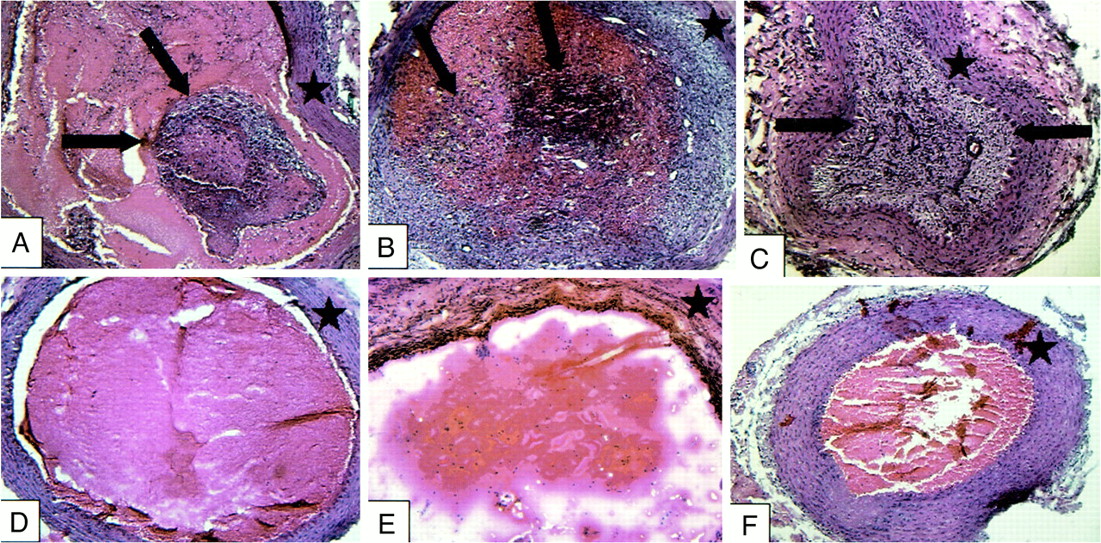

Treatment vessels containing implanted fibroblasts (A–C) and control vessels (D–F) at 3-day (A and D), 7-day (B and E), and 14-day (C and F) intervals. Treatment vessels show progressive intraluminal cellular proliferation and fibrosis (arrows). Control vessels are filled with unorganized thrombus with scant cellular infiltration. Star indicates vessel wall

Fluorescent cells with the characteristic histologic appearance of fibroblasts were present in all of the treatment vessel segments and none of the control vessel segments (Figs 7 and 8). The estimated percent fibrosis of the treatment and control vessels at the various time points is demonstrated in Figure 9. The control group vessel segments were filled predominately with unorganized thrombus containing a scant cellular infiltrate. The treatment vessels had evidence of organizing fibroblast proliferation at 3 days. This progressed to complete obliteration of the vessel lumen, with organized cellular infiltrate at the 14-day data point.